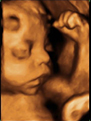

Ver la cara de un feto en rotación es posible gracias a esta ecografía en 4D. El ultrasonido es capaz de ofrecer un fiel reflejo de los rasgos faciales del bebé, que ya se encuentra en su tercer trimestre de gestación.

Ecografía 4D de la cara de un bebé en el tercer trimestre de embarazo

Vemos un primer plano en rotación del rostro de un feto en el tercer trimestre de embarazo. Los rasgos faciales del niño se perfilan con gran claridad en este examen ecográfico.